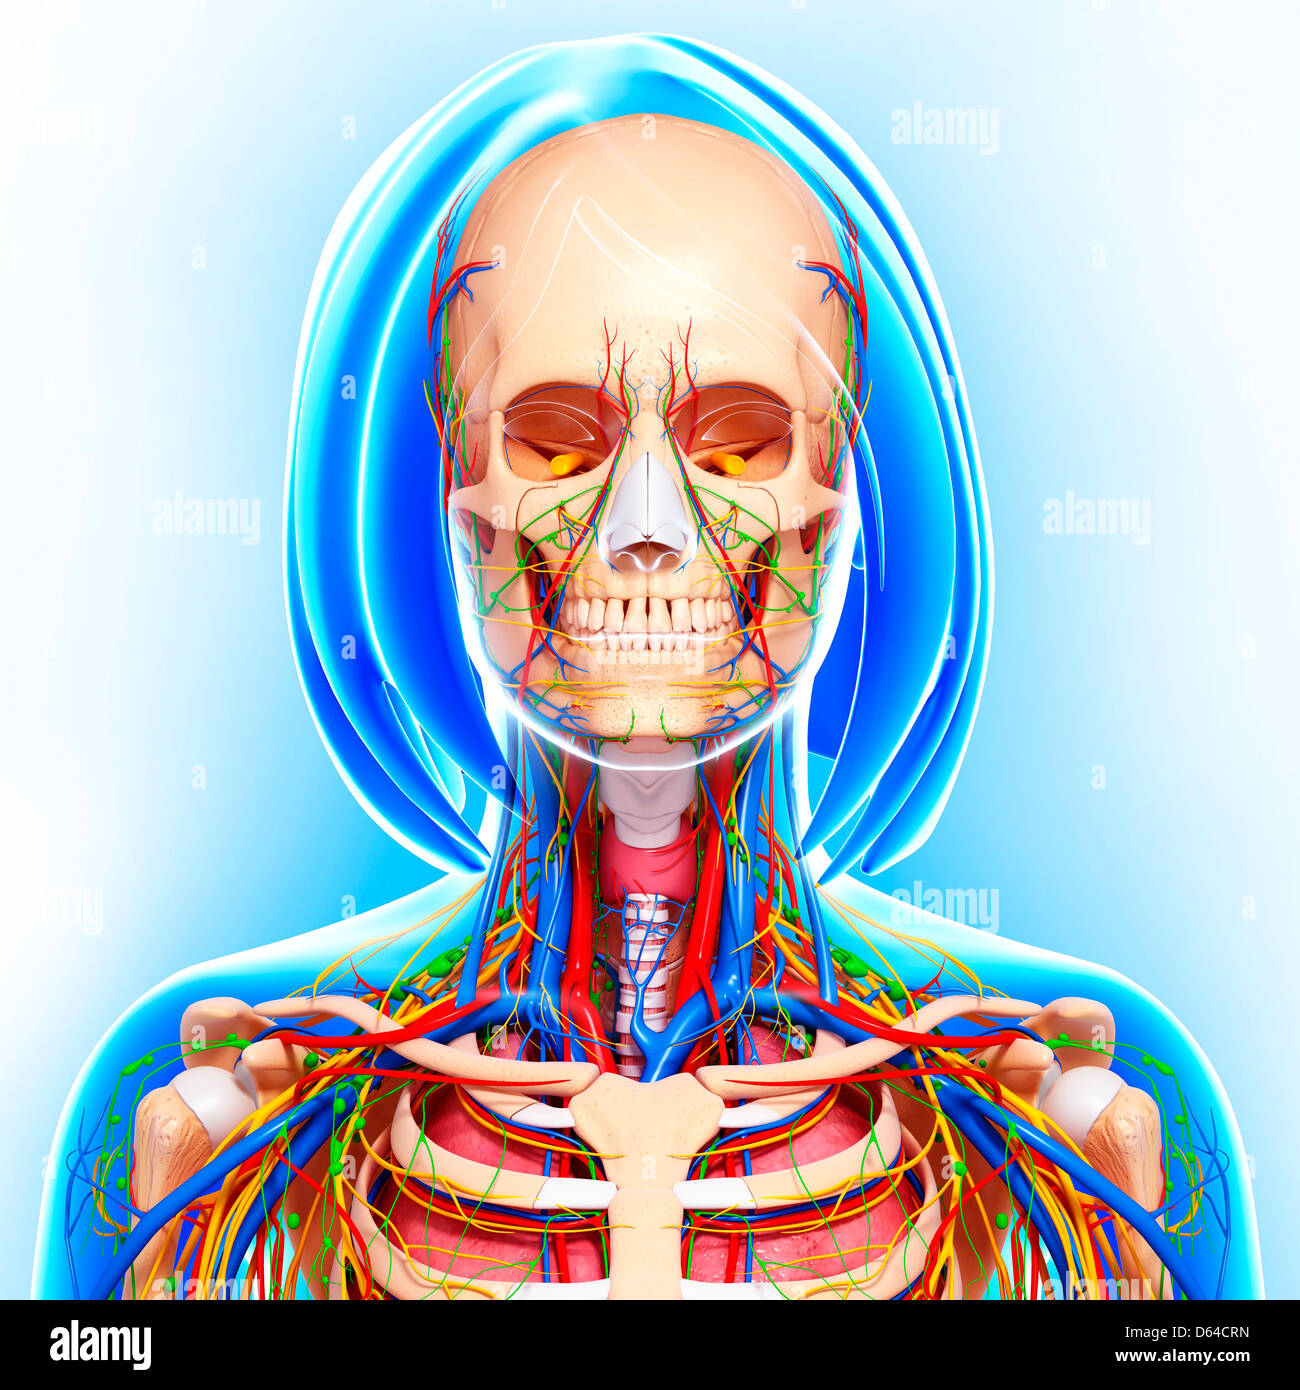

fineartamerica.comFemale Anatomy, Artwork Stock Photo - Alamy

fineartamerica.comFemale Anatomy, Artwork Stock Photo - Alamy

fineartamerica.comFemale Anatomy, Artwork Stock Photo - Alamy

fineartamerica.comFemale Anatomy, Artwork Stock Photo - Alamy

www.alamy.comFemale Anatomy, Artwork Stock Photo - Alamy

www.alamy.comFemale Anatomy, Artwork Stock Photo - Alamy

bocadowasubo.github.ioFemale Anatomy, Artwork Stock Photo - Alamy

bocadowasubo.github.ioFemale Anatomy, Artwork Stock Photo - Alamy

fineartamerica.comFemale Anatomy, Artwork Stock Photo - Alamy

fineartamerica.comFemale Anatomy, Artwork Stock Photo - Alamy

www.etsy.comFemale Anatomy, Artwork Stock Photo - Alamy

www.etsy.comFemale Anatomy, Artwork Stock Photo - Alamy

www.alamy.comFemale Anatomy, Artwork Stock Photo - Alamy

www.alamy.comFemale Anatomy, Artwork Stock Photo - Alamy

www.alamy.comFemale Anatomy, Artwork Stock Photo - Alamy

www.alamy.comFemale Anatomy, Artwork Stock Photo - Alamy

fineartamerica.comFemale Anatomy, Artwork Stock Photo - Alamy

fineartamerica.comFemale Anatomy, Artwork Stock Photo - Alamy

Female Anatomy, Artwork Stock Photo - Alamy

www.alamy.comFemale Anatomy, Artwork Stock Photo - Alamy

www.alamy.comFemale Anatomy, Artwork Stock Photo - Alamy

www.etsy.comFemale Anatomy, Artwork Stock Photo - Alamy

www.etsy.comFemale Anatomy, Artwork Stock Photo - Alamy

www.alamy.comFemale Anatomy, Artwork Stock Photo - Alamy

www.alamy.comFemale Anatomy, Artwork Stock Photo - Alamy

www.alamy.comFemale Anatomy, Artwork Stock Photo - Alamy

www.alamy.comFemale Anatomy, Artwork Stock Photo - Alamy

Female Anatomy, Artwork Stock Photo - Alamy

www.alamy.com3d Rendered Illustration Of The Female Anatomy Stock Photo - Alamy

www.alamy.com3d Rendered Illustration Of The Female Anatomy Stock Photo - Alamy

fineartamerica.com3d Rendered Illustration Of The Female Anatomy Stock Photo - Alamy

fineartamerica.com3d Rendered Illustration Of The Female Anatomy Stock Photo - Alamy

pixels.comFemale Anatomy, Artwork Stock Photo - Alamy

pixels.comFemale Anatomy, Artwork Stock Photo - Alamy